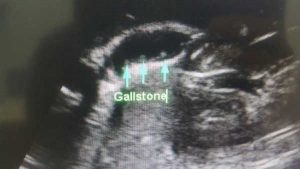

BATU KARANG DALAM HEMPEDU.

Tanda-tanda batu karang dalam hempedu adalah : 1. Sakit berpanjangan di bahagian kanan atas abdomen dan diselangi dengan loya dan muntah. 2. Demam 3. Sakit perut, loya dan muntah-muntah.…